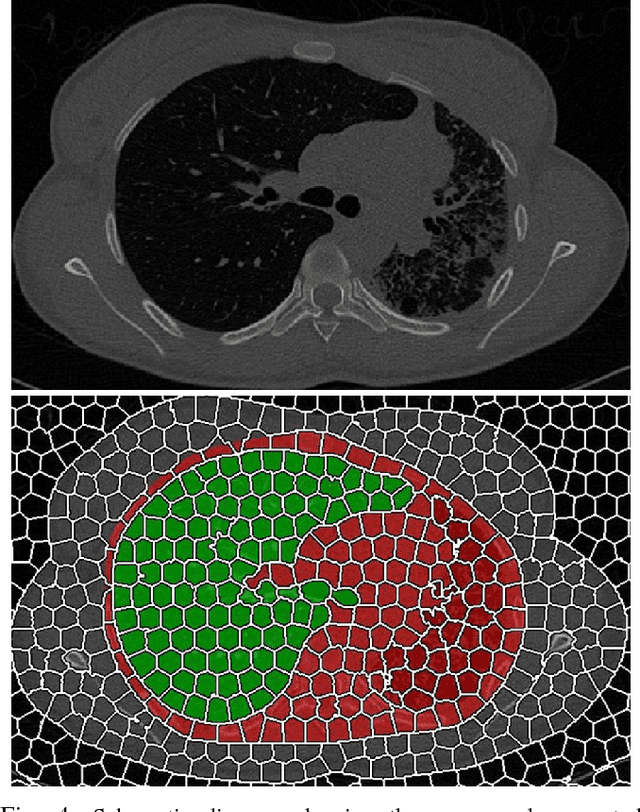

Abstract:Accurate delineation of pathological lungs from computed tomography (CT) images remains mostly unsolved because available methods fail to provide a reliable generic solution due to high variability of abnormality appearance. Local descriptor-based classification methods have shown to work well in annotating pathologies; however, these methods are usually computationally intensive which restricts their widespread use in real-time or near-real-time clinical applications. In this paper, we present a novel approach for fast, accurate, reliable segmentation of pathological lungs from CT scans by combining region-based segmentation method with local descriptor classification that is performed on an optimized sampling grid. Our method works in two stages; during stage one, we adapted the fuzzy connectedness (FC) image segmentation algorithm to perform initial lung parenchyma extraction. In the second stage, texture-based local descriptors are utilized to segment abnormal imaging patterns using a near optimal keypoint analysis by employing centroid of supervoxel as grid points. The quantitative results show that our pathological lung segmentation method is fast, robust, and improves on current standards and has potential to enhance the performance of routine clinical tasks.